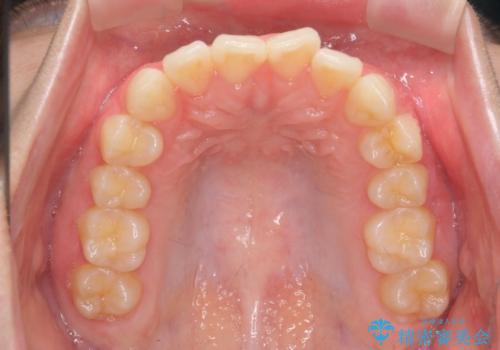

前歯のねじれをマウスピース矯正で治したい

- 前歯のねじれや がたつきを治したい、マウスピース矯正治療を希望され来院されました。

初診時程度のがたつきやねじれであれば、26枚以下のマウスピース矯正 モデレートプランで、比較的リーズナブルに矯正治療を受けていただくことができます。

実際の治療期間は約半年で仕上がりのような綺麗な歯並びを手に入れることができました。